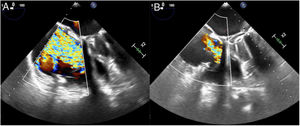

The procedure was performed under general anesthetic and with fluoroscopic and transesophageal echocardiographic guidance. The left femoral artery was cannulated for right coronary artery catheterization with a guide catheter, and an angioplasty guidewire was inserted as a marker of the tricuspid annulus. Via right femoral venous access, a 24 Fr steerable sheath from the Cardioband deployment system was introduced into the right atrium. Through this, a guide catheter was advanced to the site of attachment of the band, containing the implant catheter that deploys the anchors to fix the band to the tricuspid annulus. The implant was attached starting at the anteroseptal commissure, 25 mm from the aortic valve, and running clockwise to the posteroseptal commissure. As the guide catheter was withdrawn to expose the Dacron band, the band was fixed to the annulus with 16 screws: 3 within the first 10mm and then 1 every 8mm. Once implanted, the guide catheter and implant catheter were withdrawn and a separate catheter was introduced to adjust the size of the implant, reducing the septolateral diameter of the tricuspid annulus by cinching the wire inside the Cardioband, from 50 to 36 mm on echocardiography. After the annulus had been adjusted, 2 stenoses were observed in the middle segment of the right coronary artery, probably caused by the traction exerted, the long-term significance of which is unknown (). At the end of the procedure, the patient had moderate TR (figure 2, ). She was discharged 2 days later having improved clinically and functionally (New York Heart Association functional class II); at 1-month postdischarge she had no signs of right heart failure.